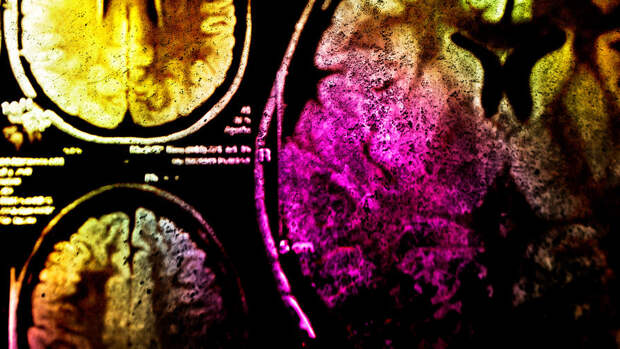

Врачи отмечают, что в таком случае снижается питание клеток мозга кислородом", — сказала она.При тяжелом течении болезни могут появиться и более серьезные расстройства, так как COVID-19 в этом случае повреждает нервные волокна и вызывает отек головного мозга.